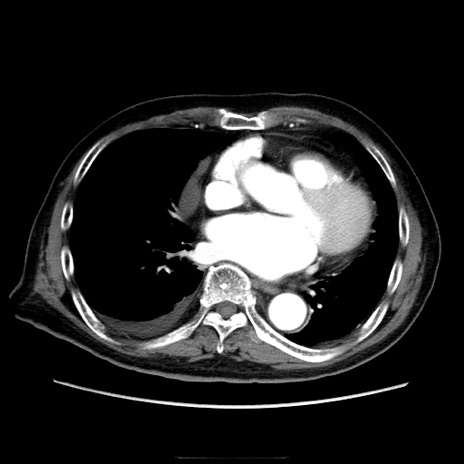

症例21(横断像)

【症例】70歳代男性

【主訴】腹痛

【現病歴】肝硬変・肝細胞癌にてかかりつけの方。約9時間前に食後より腹痛出現。症状が徐々に増悪し、嘔吐出現したため来院。

【既往歴】肝硬変、肝細胞癌(RFA、TACE後)

【身体所見】意識清明、表情苦悶様、BT 36℃、BP 129/78mmHg、P 88bpm、SpO2 97%(RA)、右上腹部から心窩部にかけて圧痛あり、反跳痛なし、筋性防御あり。

【データ】WBC 5800、CRP 0.16